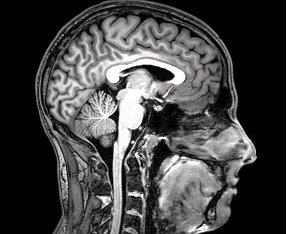

An FMRI brain scan. Image via Wikimedia Commons/user:DrOONeil. (CCA-BY-3.0).

The impact from behind may also cause a motorist’s head to move forward and strike a surface. In some situations, their head may impact the steering wheel. In other situations, they may move forward with so much force that they impact the windshield. If the impact is slightly off-center, their heads may strike the side window or roll cage. All of these situations can lead to serious head injuries that may cause a range of both physical and psychological impairments. Loss of motor control can result from a head injury, and personality changes are not unheard of. In the most serious examples of head injuries, victims can fall into comas2, and they may remain in a vegetative state for decades or even the rest of their lives. Enlist the Help of a Qualified Attorney TodayIf you’ve been rear-ended by a semi-truck in New Orleans, you may be asking yourself: “Where can I find truck accident attorneys near me?” Truth be told, you don’t have to look very hard to find legal professionals who can assist you. Truck accident attorneys are standing by, ready to guide you towards a fair, adequate settlement. All you need to do is reach out and book your consultation. Sources: